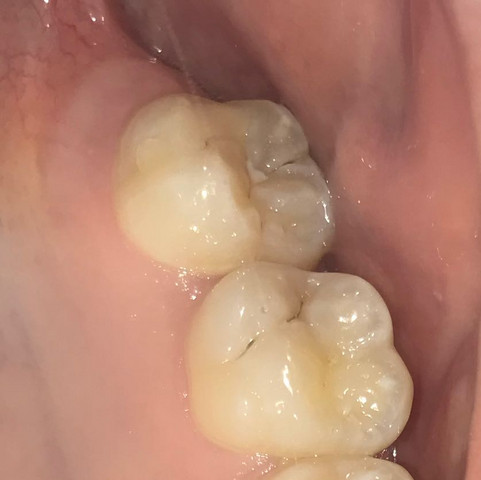

Beginnende Karies, also eine zunächst unsichtbare, oberflächliche Entmineralisierung des Zahnschmelzes, lässt sich durch Fluoride in der Zahnpasta rückgängig machen Im weiteren Kariesverlauf unterscheiden Experten vier Stufen Schreitet die Entmineralisierung des Zahnschmelzes weiter voran, entstehen weiße Flecken auf den Zähnen. Die häufigste Ursache für weiße Flecken auf den Zähnen ist eine Demineralisation des Zahnschmelzes Diese Form der Aufhellung ist das Anfangsstadium der Karies Besonders die Träger von festen Zahnspangen entwickeln unter den aufgeklebten Brackets weiße Flecken, da der Zahnschmelz unter dem Kleber Mineralien verliert Aber auch ohne Zahnspange kann der Zahnschmelz angegriffen werden und. Karies im Frühstadium Außerdem können weiße Flecken über die Entmineralisierung von Zahnschmelz.

Weiße Flecken im Zahnschmelz, die ersten sichtbaren Anzeichen einer beginnenden Karies, verschwinden wieder ICON® wird von unseren Patienten durchweg positiv beurteilt, und wir selbst haben mit diesem Verfahren nur beste Erfahrungen gemacht. Zur Behandlung bei Karies im Anfangsstadium als Auslöser genügt oftmals die Zugabe von Fluorid, um Löcher in den Zähnen zu vermeiden Zum Teil ist eine geringe Bohrung notwendig, um das bereits entstandene Loch zu behandeln. Einer „echten Karies“ geht in jedem Fall ein Entkalkungsprozess im Bereich des Zahnschmelzes voraus (Initialkaries)Diese Entkalkungen sind als kleine weiße Flecken, so genannte „White Spots“ auf der Zahnoberfläche sichtbar und mit einfachen Mitteln schnell in den Griff zu bekommen Es empfiehlt sich das Anwenden von fluoridhaltigen Zahncremes, die den Zahn remineralisieren und von.

Erste Anzeichen beginnender Karies können kreidigweiße Flecken auf der Zahnoberfläche sein Verschiedene Maßnahmen sollen das Voranschreiten der Karies in diesem Stadium verhindern Sie zielen darauf ab, das übermäßige Herauslösen von Mineralien aus den Zähnen zu stoppen Zudem sollen Mineralien wieder in die Zähne eingelagert werden. Weiße Flecken im Zahnschmelz, die ersten sichtbaren Anzeichen einer beginnenden Karies, verschwinden wieder ICON® wird von unseren Patienten durchweg positiv beurteilt, und wir selbst haben mit diesem Verfahren nur beste Erfahrungen gemacht. Weiße Flecken auf den Zähnen können ein erstes Anzeichen für Karies sein Erfahren Sie hier mehr über die Symptome bei Karies Zahnbelag (Plaque) entsteht ständig neu – auch schon kurz nach dem Zähneputzen.

Erste Anzeichen beginnender Karies können kreidigweiße Flecken auf der Zahnoberfläche sein Verschiedene Maßnahmen sollen das Voranschreiten der Karies in diesem Stadium verhindern Sie zielen darauf ab, das übermäßige Herauslösen von Mineralien aus den Zähnen zu stoppen Zudem sollen Mineralien wieder in die Zähne eingelagert werden. Weiße Flecken auf den Zähnen können aber nicht nur ein ästhetisches, sondern auch ein medizinisches Problem sein und die Gesundheit Ihrer Zähne beeinträchtigen In den folgenden Absätzen erfahren Sie, worum es sich bei den weißen Flecken auf Ihren Zähnen handeln könnte, was Sie dagegen unternehmen können und wie Sie in Zukunft. Weisse Flecken auf den Zähnen können ein erstes Anzeichen für Karies sein Erfahren Sie hier mehr über die Symptome bei Karies Schmerzempfindliche Zähne können ein Anzeichen für Zahnschmelzabbau sein Mehr erfahren Zahnbelag kann nur mechanisch, das heisst mit Zahnbürste und Zahnseide, entfernt werden.